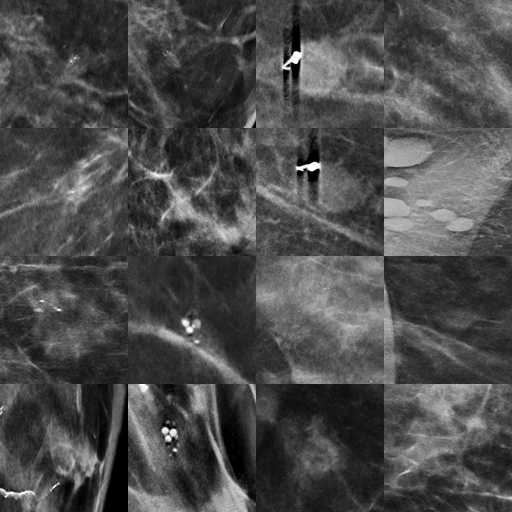

In Fig. 3, we qualitatively compare lesions in the EMBED and T-SYNTH datasets. We find that the EMBED bounding boxes may contain multiple lesions and may not be as consistently labeled as the bounding boxes in the T-SYNTH dataset.

(a) EMBED Lesions

Refer to caption

(b) T-SYNTH Lesions

Figure 3: Feature analysis of lesions in the EMBED and T-SYNTH datasets.